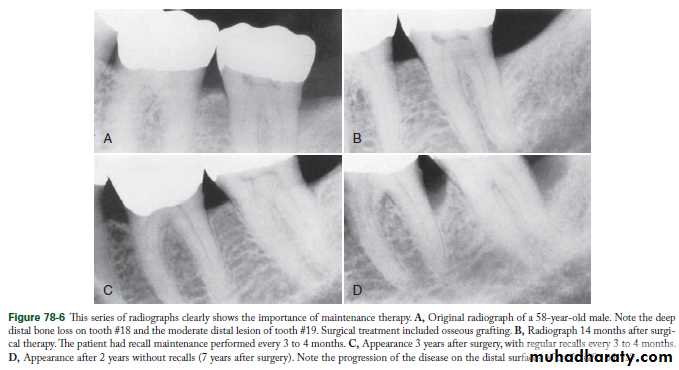

Transfer of the patient from active treatment status to a maintenance program is a definitive step in total patient care that requires time and effort on the part of the dentist and staff. Patients must understand the purpose of the maintenance program, and the dentist must emphasize that preservation of the teeth depends on maintenance therapy. Patients who are not maintained in a supervised recall program subsequent to active treatment show obvious signs of recurrent periodontitis (e.g., increased pocket depth, bone loss, or tooth loss).

Periodic recall visits form the foundation of a meaningful longterm prevention program. The interval between visits is initially set at 3 months but may be varied according to the patient’s needs. Periodontal care at each recall visit comprises three parts:The first part involves examination and evaluation of the patient’s current oral health. The second part includes the necessary maintenance treatment and oral hygiene reinforcement. The third part involves scheduling the patient for the next recall appointment, additional periodontal treatment, or restorative dental procedures.